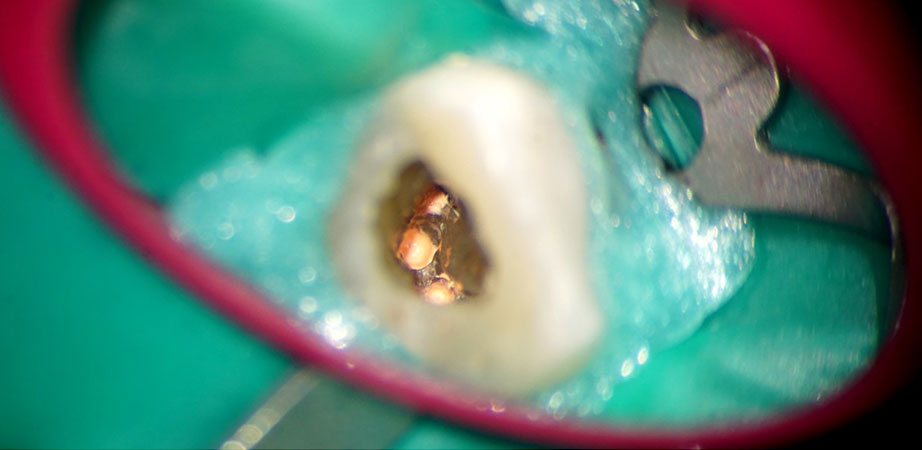

The surgical microscope helps visualize and magnify structures up to 25 times their actual size. This allows for observation and treatment of problems which cannot be seen with the naked eye. Dr. Siju Jacob is among a select group of clinicians who have been practicing microscopic endodontics since 2004. The main advantage of this procedure – unparalleled precision!

4) Photographs of each step of the root canal treatment can be taken and e-mailed to the patient.

Photographs of the procedure are e-mailed to the patient. Overseas patients can forward the work done to their family dentist back home. This ensures total transparency in the treatment done.